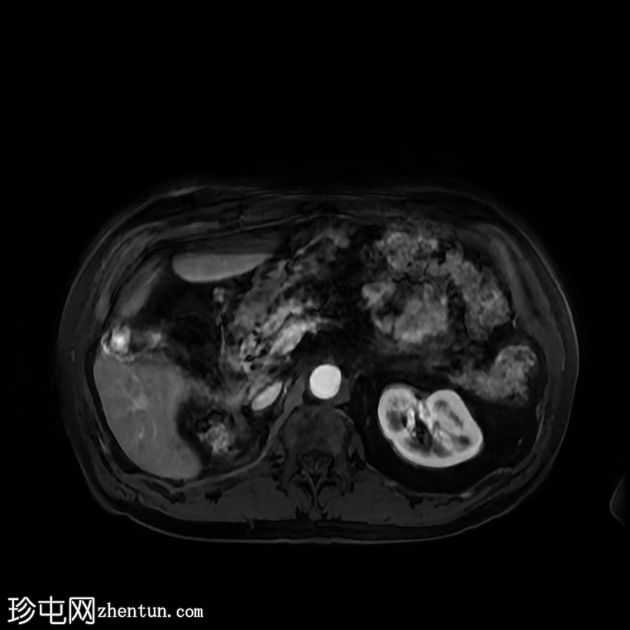

轴位

T2加权像

行MRI检查以明确病因。 MRI显示胆囊底部有一孤立性息肉样病变,突入胆囊内,大小约为21 mm x 17 mm。病变表面可见高T1信号,可能代表血液成分。病变早期增强扫描后强化程度较正常胆囊壁更为明显。